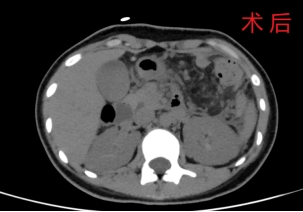

在麻醉科、手术室等多科室通力配合下,孔瑞和胡继盛团队全程在微创下通过腹部上5个1-2cm的切口进行操作,将肿瘤从脾血管上完整游离下来,保留了脾脏血管,同时保留了脾脏的功能。手术历时4个小时,顺利完成。术后病理回报为胰腺粘液性囊腺瘤,具有一定的恶变潜能。术后病人病情平稳,第二天就能离床活动并少量饮水,在治疗组医生和护士的精心护理下,患者很快顺利出院。

孔瑞介绍,该患者肿瘤体积大,与周围脏器粘连严重,特别是与脾门区血管粘连较重,腹腔镜下操作难度较大。考虑到病人年龄小,尽可能保留器官功能更有利于病人的远期预后,因此对病人实施了腹腔镜下保留脾脏胰体尾切除,切除肿瘤的同时完整保留脾血管和脾脏,与传统胰体尾脾切除相比较,更进一步增加了手术难度。